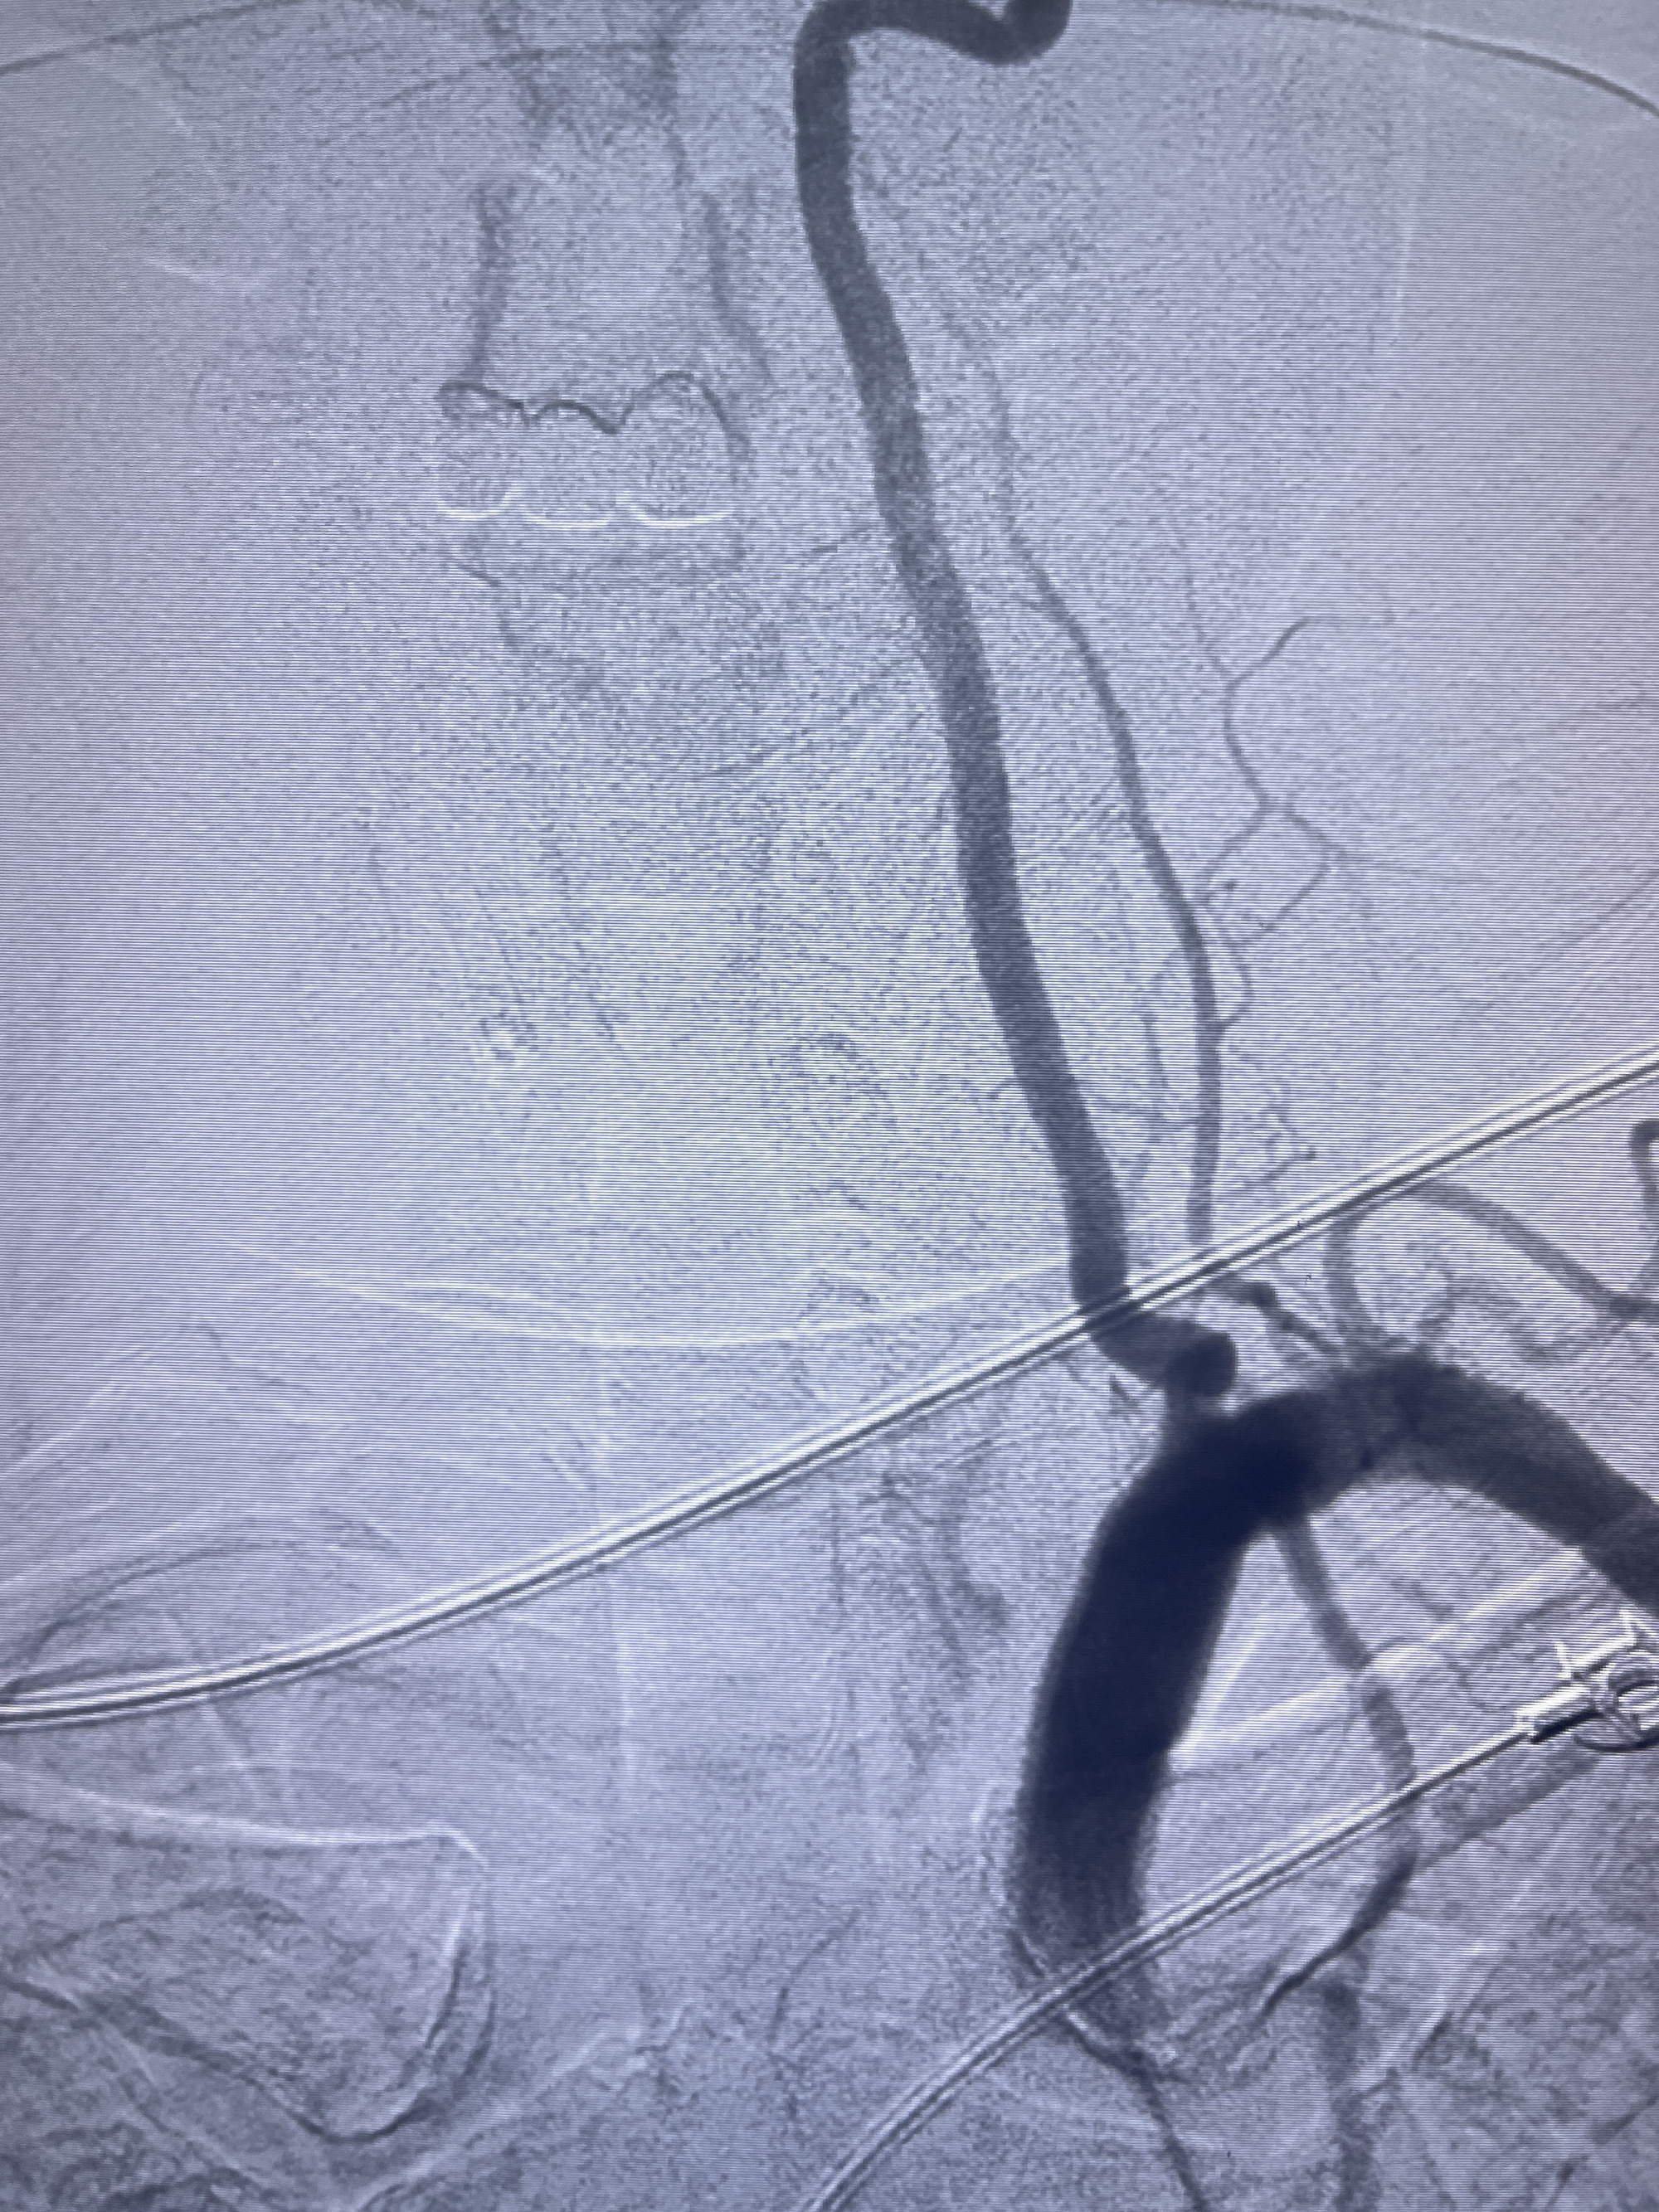

202.04.28脑血管造影:右侧大脑后动脉远段闭塞,右侧椎动脉V4段可见“囊状造影剂填充影”,大小7.64*7.65mm,可见PICA由动脉瘤发出;

治疗策略:

1.普通支架辅助弹簧圈栓塞?

2.密网支架辅助弹簧圈栓塞?